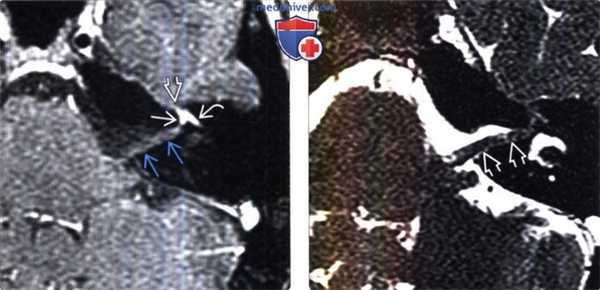

(Слева) МРТ, постконтрастное Т1-ВИ, режим подавления сигнала от жира, аксиальный срез: у пациента с выраженным длительное время сохраняющимся параличом Белла определяется интенсивное контрастирование лабиринтного, переднего барабанного участков лицевого нерва, а также коленчатого ганглия. «Хохолок» во ВСП простирается вдоль лицевого нерва, достигая внутреннего слухового отверстия, и визуализируется в виде менее интенсивного участка контрастирования.

(Справа) Тонкосрезовая (1 мм) МРТ, Т2-ВИ, режим подавления сигнала от жира, аксиальный срез: у этого же пациента определяется набухание лицевого нерва в области его канала.

(Слева) При аксиальной МРТ Т1 ВИ C+ FS у пациента с тяжелым параличом Белла, протекающим без ремиссий, определяется интенсивное контрастирование коленчатою ганглия, лабиринтной, передней барабанной части лицевого нерва. «Хохолок» идет по ходу лицевого нерва в ВСК в виде менее выраженного участка накопления контраста, достигая слуховою отверстия.

(Справа) При аксиальной тонкосрезовой (1 мм) МРТ Т2 ВИ FS у этою же пациента в ВСК визуализируется отечный интраканаликулярный сегмент лицевого нерва.